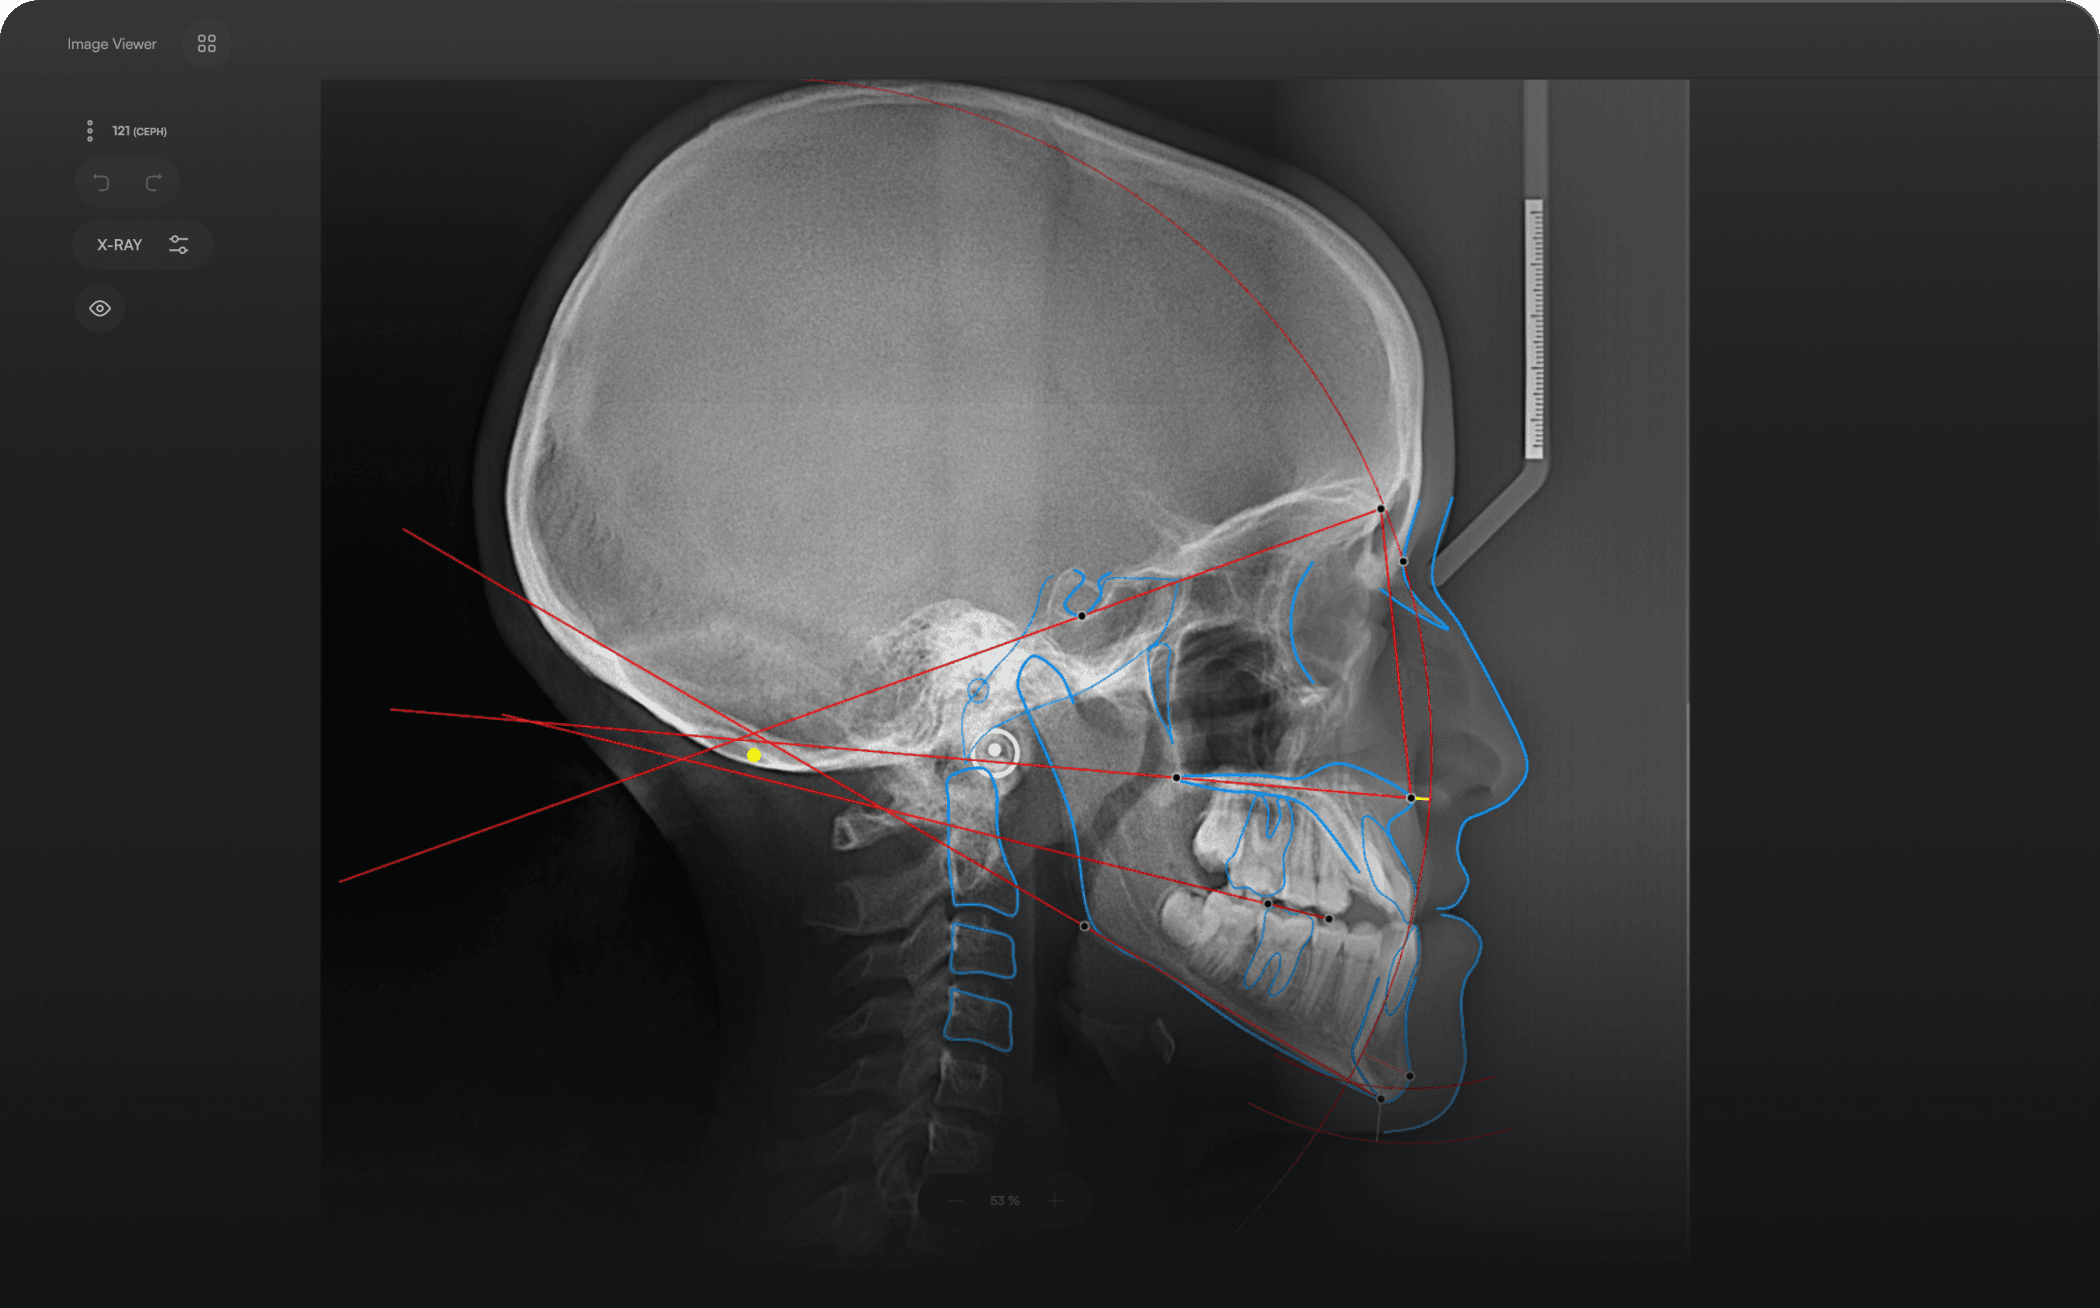

AI-driven Automated Lateral

Cephalometric Tracing

150+ landmarks traced in seconds

Automated analyses

Download detailed reports

Accurate. Fast. Effortless.

Identify 150+ orthodontic landmarks in under 10 seconds — a task that

traditionally may take more than 30 minutes.